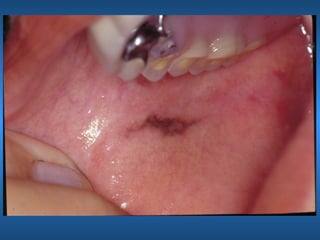

Tatuagem por Amalgama

• Impregnação

• Aspectos Clínicos Radiográficos

Pigmentação Melânica

• Características Clínicas